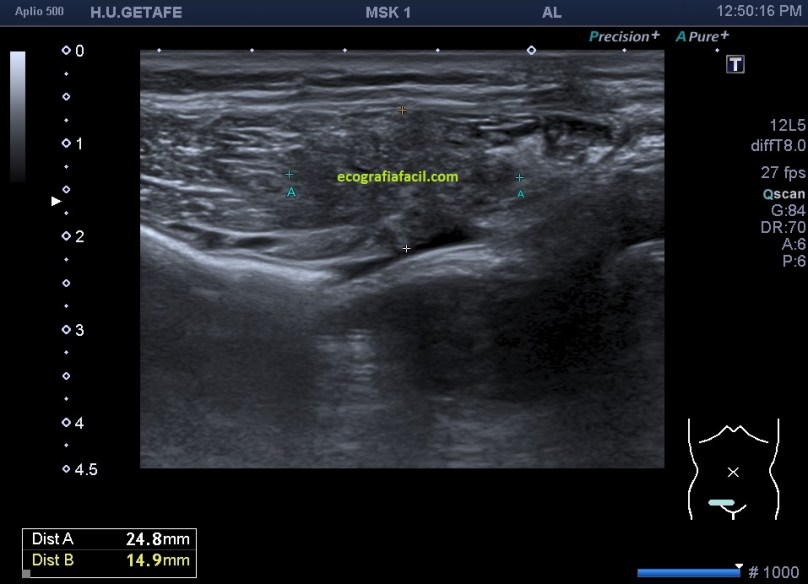

En cuanto la paciente me indicó su zona de dolor y pude el transductor observé una imagen mal definida que ocupaba la porción inferior del músculo recto abdominal derecho (coincidiendo con foco doloroso), se visualiza una lesión de ecogenicidad heterogénea (predominio hipoecogénico) con bordes irregulares de aproximadamente 2,5 cms en su eje más largo.

La imagen final demuestra una visión panorámica de los rectos abdominales inferiores demostrando los hallazgos que te he ido explicando durante el post. En este caso me hizo falta utilizar una función del ecógrafo muy útil que es la “función dual”, donde he dividido a pantalla en dos y he podido comparar en una misma imagen tanto a normalidad como la zona patológica, con un considerable aumento de la resolución de la imagen y un aumento en la calidad global de esta tanto en corte transverso como en longitudinal. Esta función dual permite el estudio comparativo con doppler. Muy útil, aunque el almacenamiento masivo de imagen en el pacs hace que esta función haya caído paulatinamente en desuso.